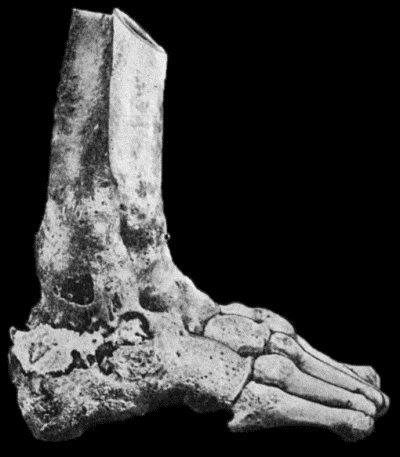

127.Advanced Tuberculous Disease in Region of Ankle 459

128.Tuberculous Dactylitis 460